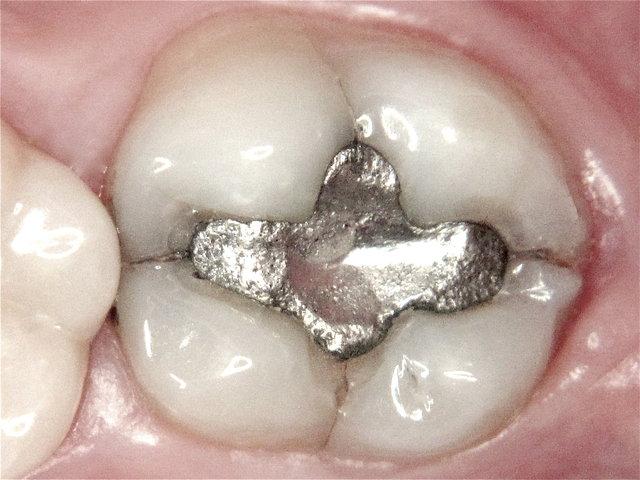

Randspalten in undichter Amalgam-Füllung ...

Composit-Füllung by CLINICDENT ✓